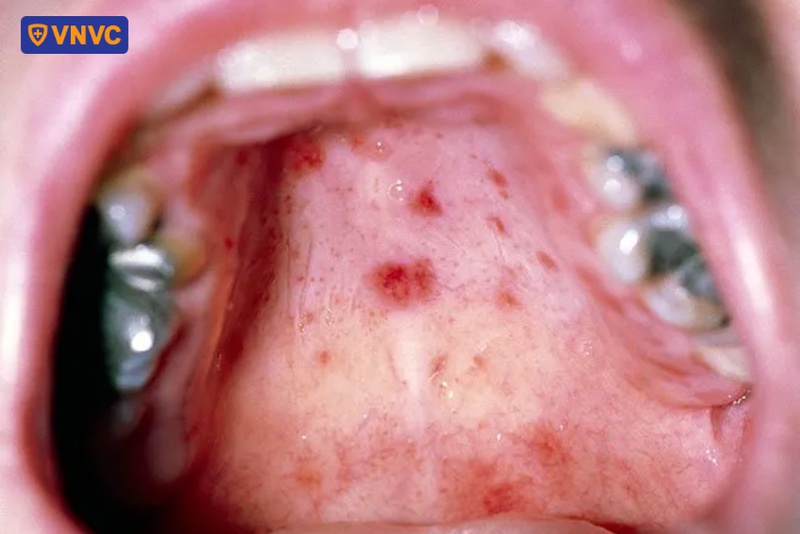

Dấu hiệu đặc trưng của bệnh tay chân miệng là tổn thương niêm mạc da chủ yếu là nổi mụn nước, sốt, đau họng... Đây là triệu chứng điển hình xuất hiện sớm trong quá trình phát triển của bệnh, thường xảy ra sau khi trẻ bị sốt và có biểu hiện mệt mỏi, chán ăn. Trong đó, nổi mụn nước thường xuất hiện ở lòng bàn tay, bàn chân, gối, mông, khoang miệng, xung quanh miệng...

- Mụn nước trong khoang miệng có thể nhanh chóng vỡ ra, tạo thành các vết loét nông, gây đau và khiến trẻ gặp khó khăn trong việc ăn uống, dẫn đến tình trạng mệt mỏi và mất nước.

Nếu các nốt mụn nước xuất hiện dày đặc trong khoang miệng của người bệnh, có thể khiến bệnh nhân đau đớn khi ăn uống, dẫn đến việc ăn ít, ăn không đủ dinh dưỡng. Tình trạng này kéo dài có thể dẫn đến thiếu chất, mất nước, cơ thể mệt mỏi và suy kiệt.

- Chăm sóc mụn nước trong miệng: Đầu tiên, khi trẻ mắc tay chân miệng và bị các vết loét ở miệng, ba mẹ cần phải vệ sinh răng miệng sạch sẽ cho trẻ bằng các dung dịch gel dạng nhũ tương chấm vào các vết loét trong khoang miệng để giảm cảm giác đau, đồng thời giúp trẻ ăn uống dễ dàng hơn. Nếu vết loét quá nhiều, bác sĩ có thể chỉ định trẻ dùng kháng sinh để tránh bội nhiễm.